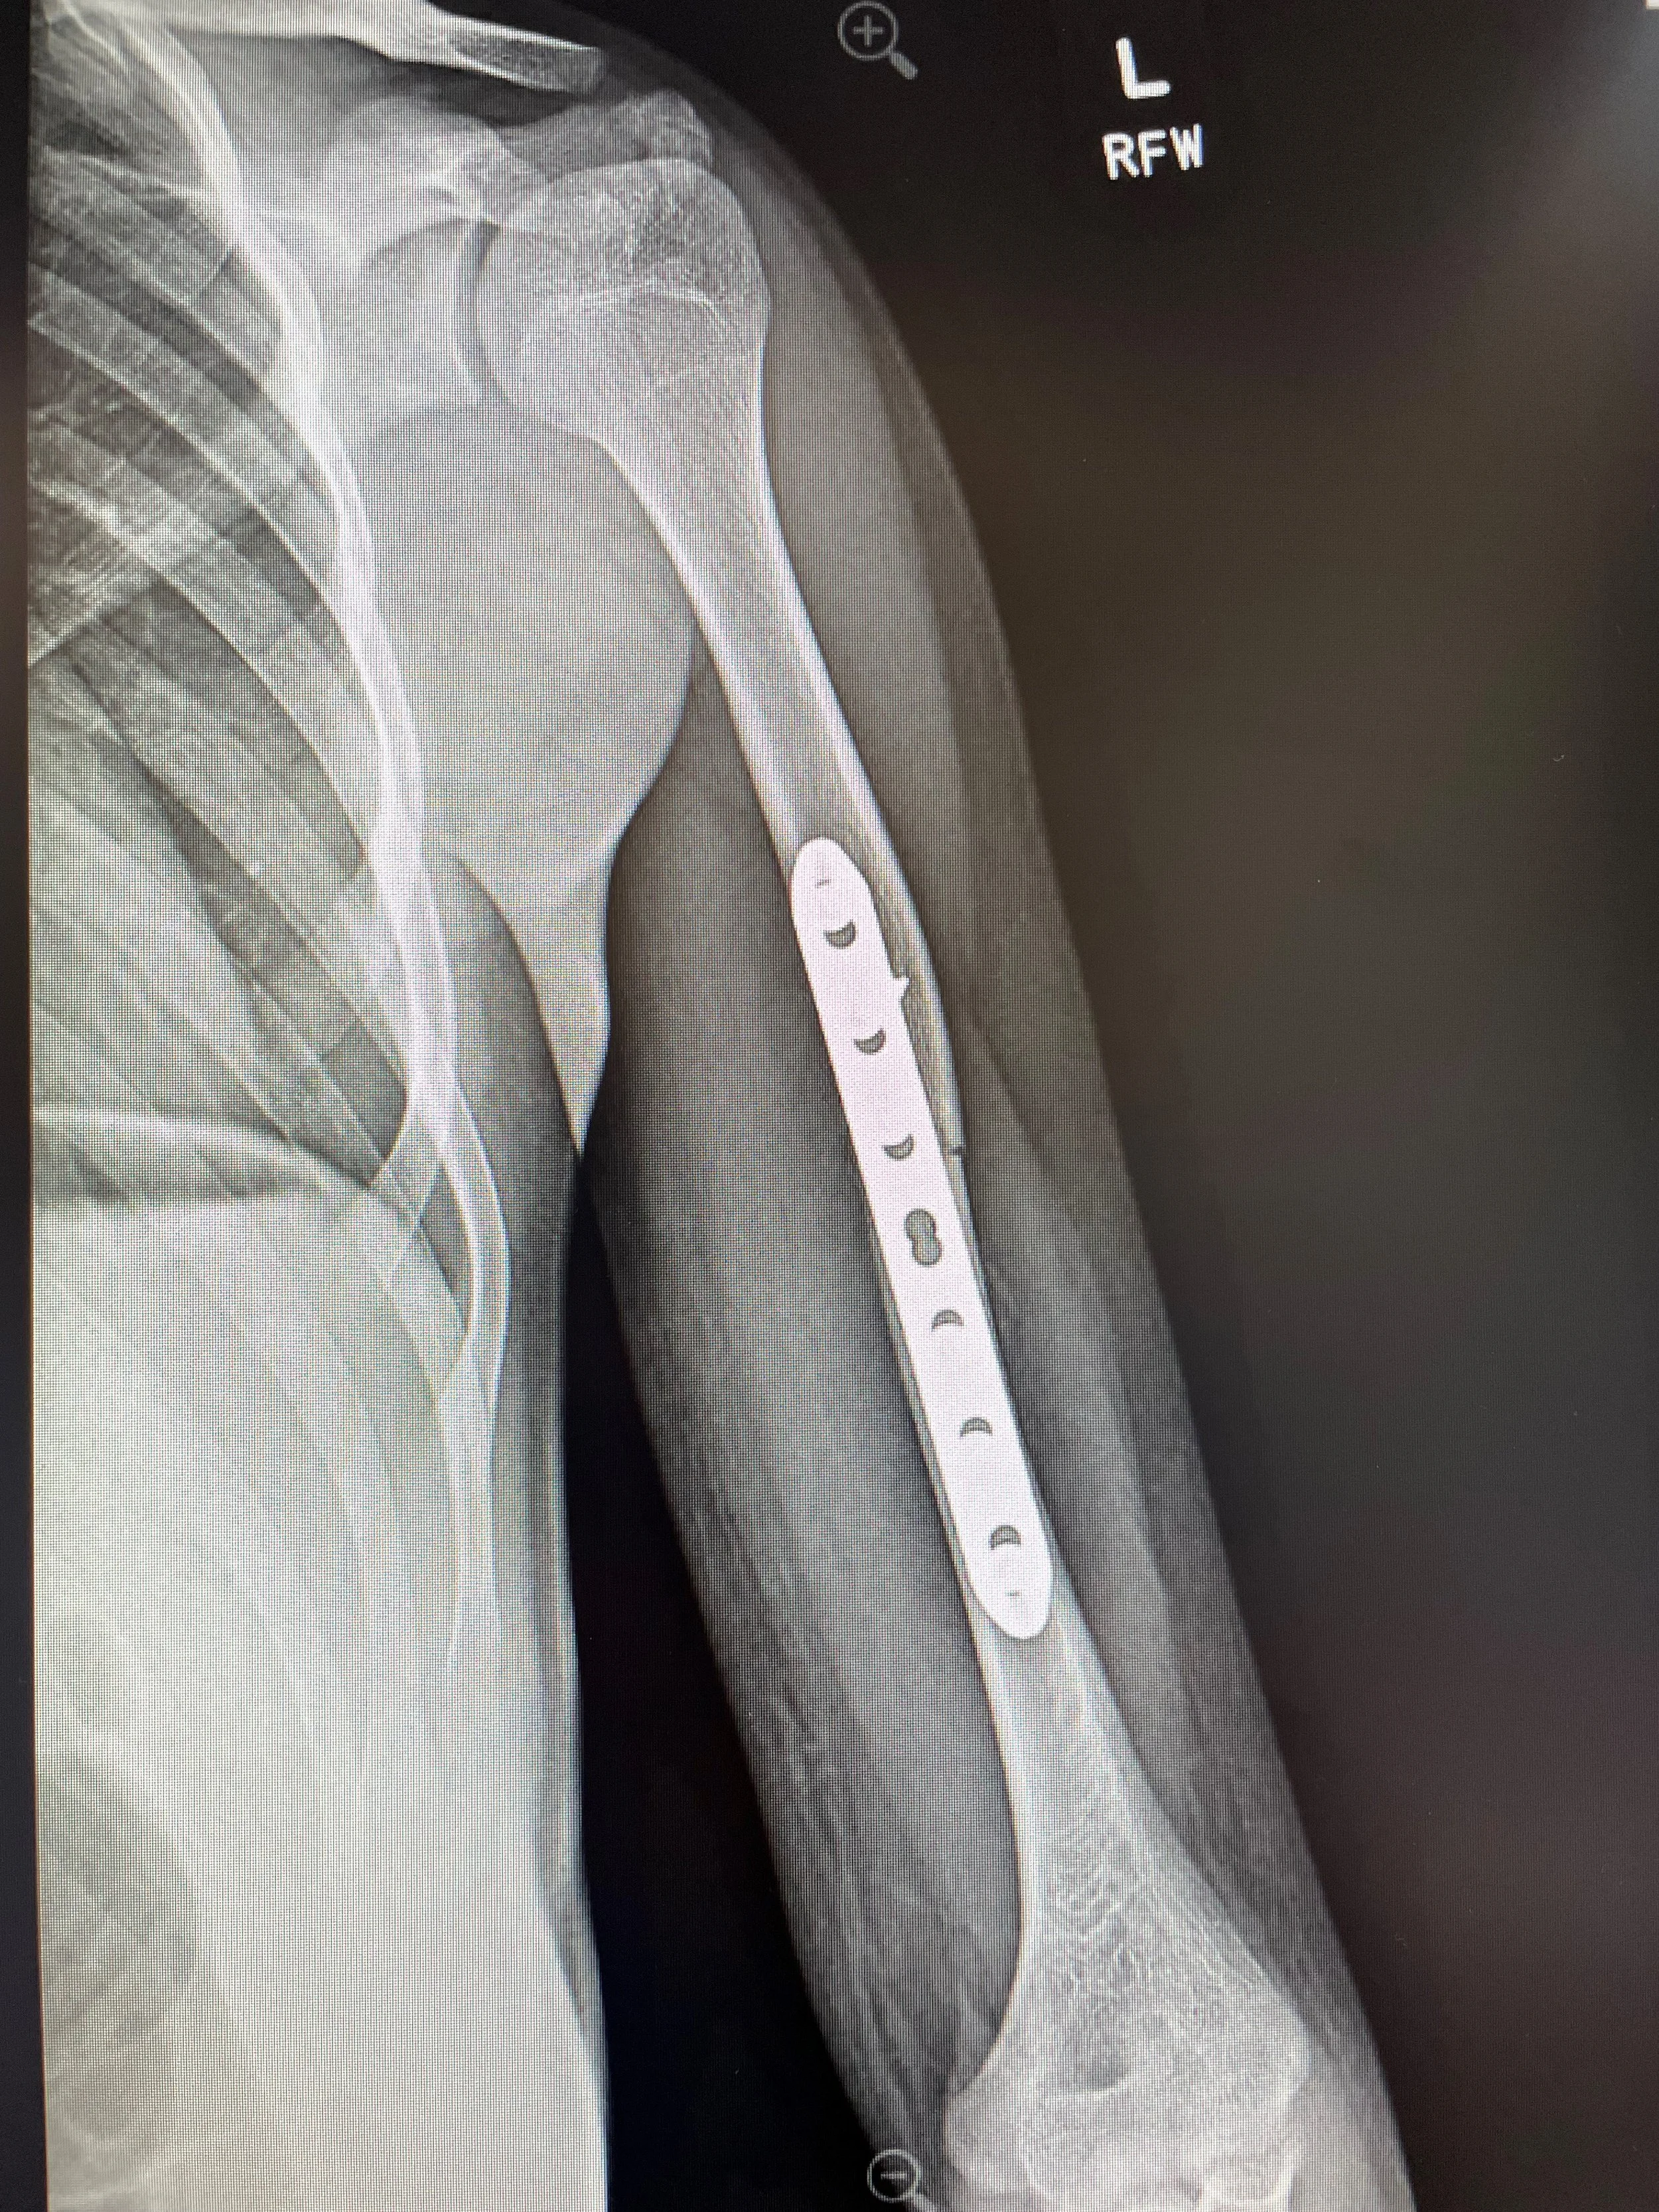

X-ray of a shoulder with a metal plate and screws used for surgical fixation of a fractured humerus.